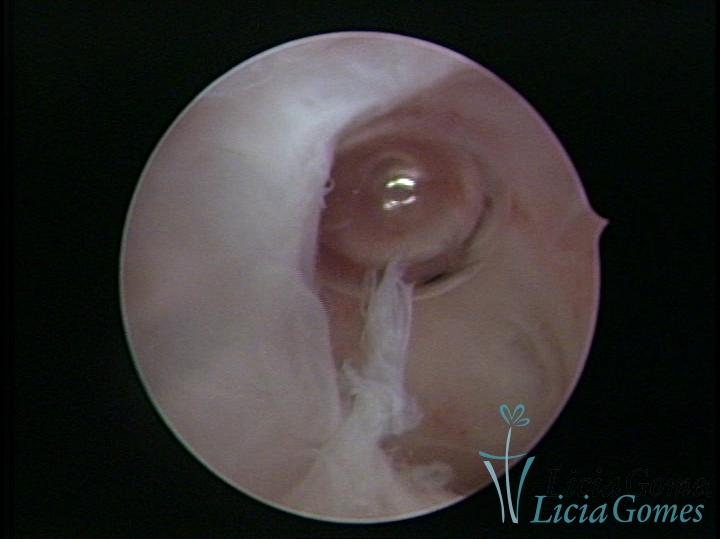

FIBROUS SYNECHIA

Uterine synechiae are scars (adherence) between the surface of the uterine walls, which may occur after the surgical procedure, uterine curettage, or after an inflammatory process in the uterine cavity (endometritis), which may lead to menstrual changes, infertility and obstetric complication such as abortion and premature birth.

• SINÉQUIA TIPO FIBROSA